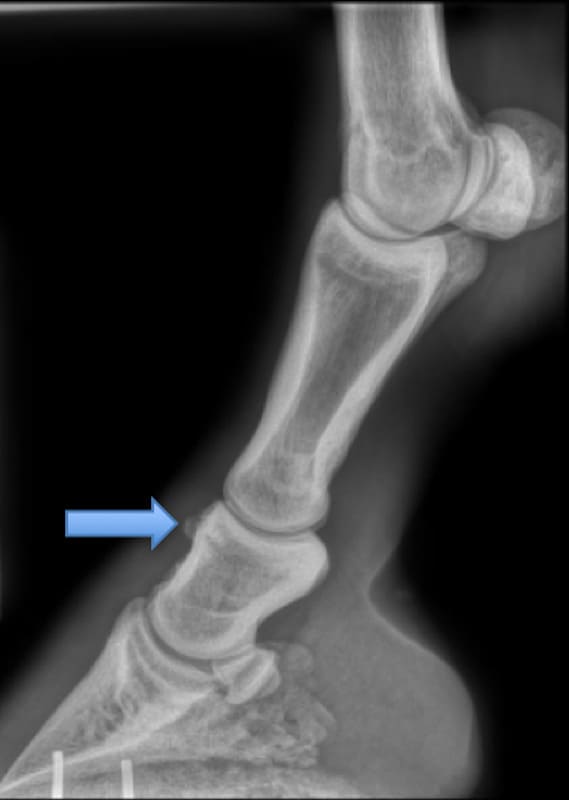

Radiographie latérale de l'arthrite de l'articulation interphalangienne proximale. La flèche montre l'ostéophytose de P2 proximale